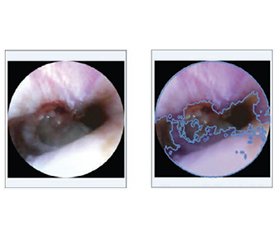

Актуальність. Точна і швидка оцінка ступеня перфорації барабанної перетинки є надзвичайно важливою в клінічній отоларингології, особливо в умовах обмежених ресурсів. Мета: розробка комп’ютерної системи із налаштовуваними інструментами сегментації, які можна швидко застосувати для поліпшення процесу оцінювання, скорочення часу, необхідного для отримання послідовних, об’єктивних і точних результатів при роботі з ендоскопічними зображеннями різної якості, контрастності, освітленості й інших змінних. Матеріали та методи. Для досягнення цієї мети розроблено спеціалізований веб-додаток із налаштовуваним адаптивним алгоритмом сегментації Flood Fill. Експерименти проводилися з використанням розробленої системи й набору ендоскопічних зображень із різними типами перфорацій, що були перевірені експертами для забезпечення якості та застосовності запропонованих моделей. Результати. Експериментальні результати продемонстрували, що адаптивний алгоритм сегментації забезпечує надійну й послідовну ідентифікацію пошкоджених ділянок, значно зменшуючи діагностичну варіативність та ймовірність неточностей. Можливість налаштування параметрів алгоритму дозволила проводити точну сегментацію навіть за неоптимальних умов зйомки (низька контрастність, розмиті зображення), вирішуючи типові клінічні проблеми. Практична корисність та інтуїтивний дизайн програми мінімізували вимоги до навчання, сприяючи потенційному швидкому клінічному впровадженню і можливості оцінювати перфорації швидше за традиційний візуальний підхід. Висновки. Запропоновані модель, метод та веб-додаток ефективно відповідають меті роботи — поліпшенню надійності діагностики й клінічного робочого процесу, заощаджуючи час спеціалістів. Розроблений інструмент має значний потенціал щодо поліпшення результатів аналізу й лікування пацієнтів в умовах надзвичайних ситуацій та обмежених ресурсів. Подальше вдосконалення за допомогою передових технологій обробки зображень може ще більше підвищити точність і застосовність в інших медичних галузях.

Background. Accurate and rapid assessment of tympanic membrane perforations is essential in clinical otolaryngology, particularly in resource-constrained environments. The purpose of the work is to develop a computer system powered by highly adjustable segmentation tools that can be quickly applied to improve the assessment, reduce the time needed for obtaining consistent, objective and precise results when dealing with endoscopic images of different quality, contrast, amount of light and other variabilities. Materials and methods. To achieve this, a specialized web-based application was developed, utilizing a modified adaptive Flood Fill segmentation algorithm. The experiments were conducted using the developed system and a dataset of endoscopic images with various types of perforations, examined by expert to ensure the quality and applicability of the proposed models. Results. Experimental results demonstrated that the adaptive segmentation algorithm provided reliable and consistent identification of damaged areas, significantly reducing diagnostic variability and probable inaccuracies. Adjustability of algorithm parameters allowed accurate segmentation even under suboptimal imaging conditions (low contrast, blurred images), addressing typical clinical challenges. The practical usability and intuitive design of the application minimized training requirements, facilitating potential rapid clinical deployment and ability to assess perforations quicker than with traditional visual approach. Conclusions. The proposed model, method and web-based application effectively meet the goal of the work — improving diagnostic reliability and the clinical workflow, saving clinicians’ time. The developed tool has substantial potential to enhance patient outcomes in emergency and resource-limited settings. Further improvement through advanced image processing techniques could increase accuracy and applicability even more broadly across other medical domains.